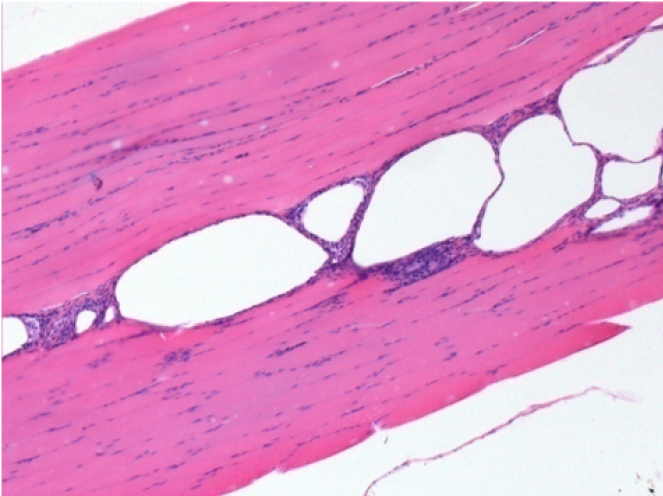

08

3 mesi dopo Iniezione di Endopeel

Scatola Nr 4

3 mesi (Giorno90) dopo iniezione 0.1ml di Endopeel nel muscolo pretibiale destro ( Dx)

Sx : Controllo-100x-Giorno90

Dx:100x-Giorno90